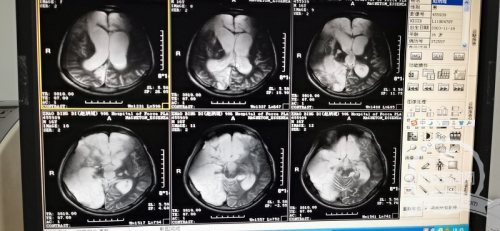

情况比想象的更糟糕,这是接诊的神经外科主任赵永博的第一反应。孩子的整个表现是一个去皮层强直的状态,四肢僵硬的让人担心一不小心会掰折,体温随时会因为肌肉强直收缩超过40℃。看着右侧大脑半球大面积梗塞的片子,相比之前治好过的不少意识障碍患者,这个患儿的治疗难度更大。